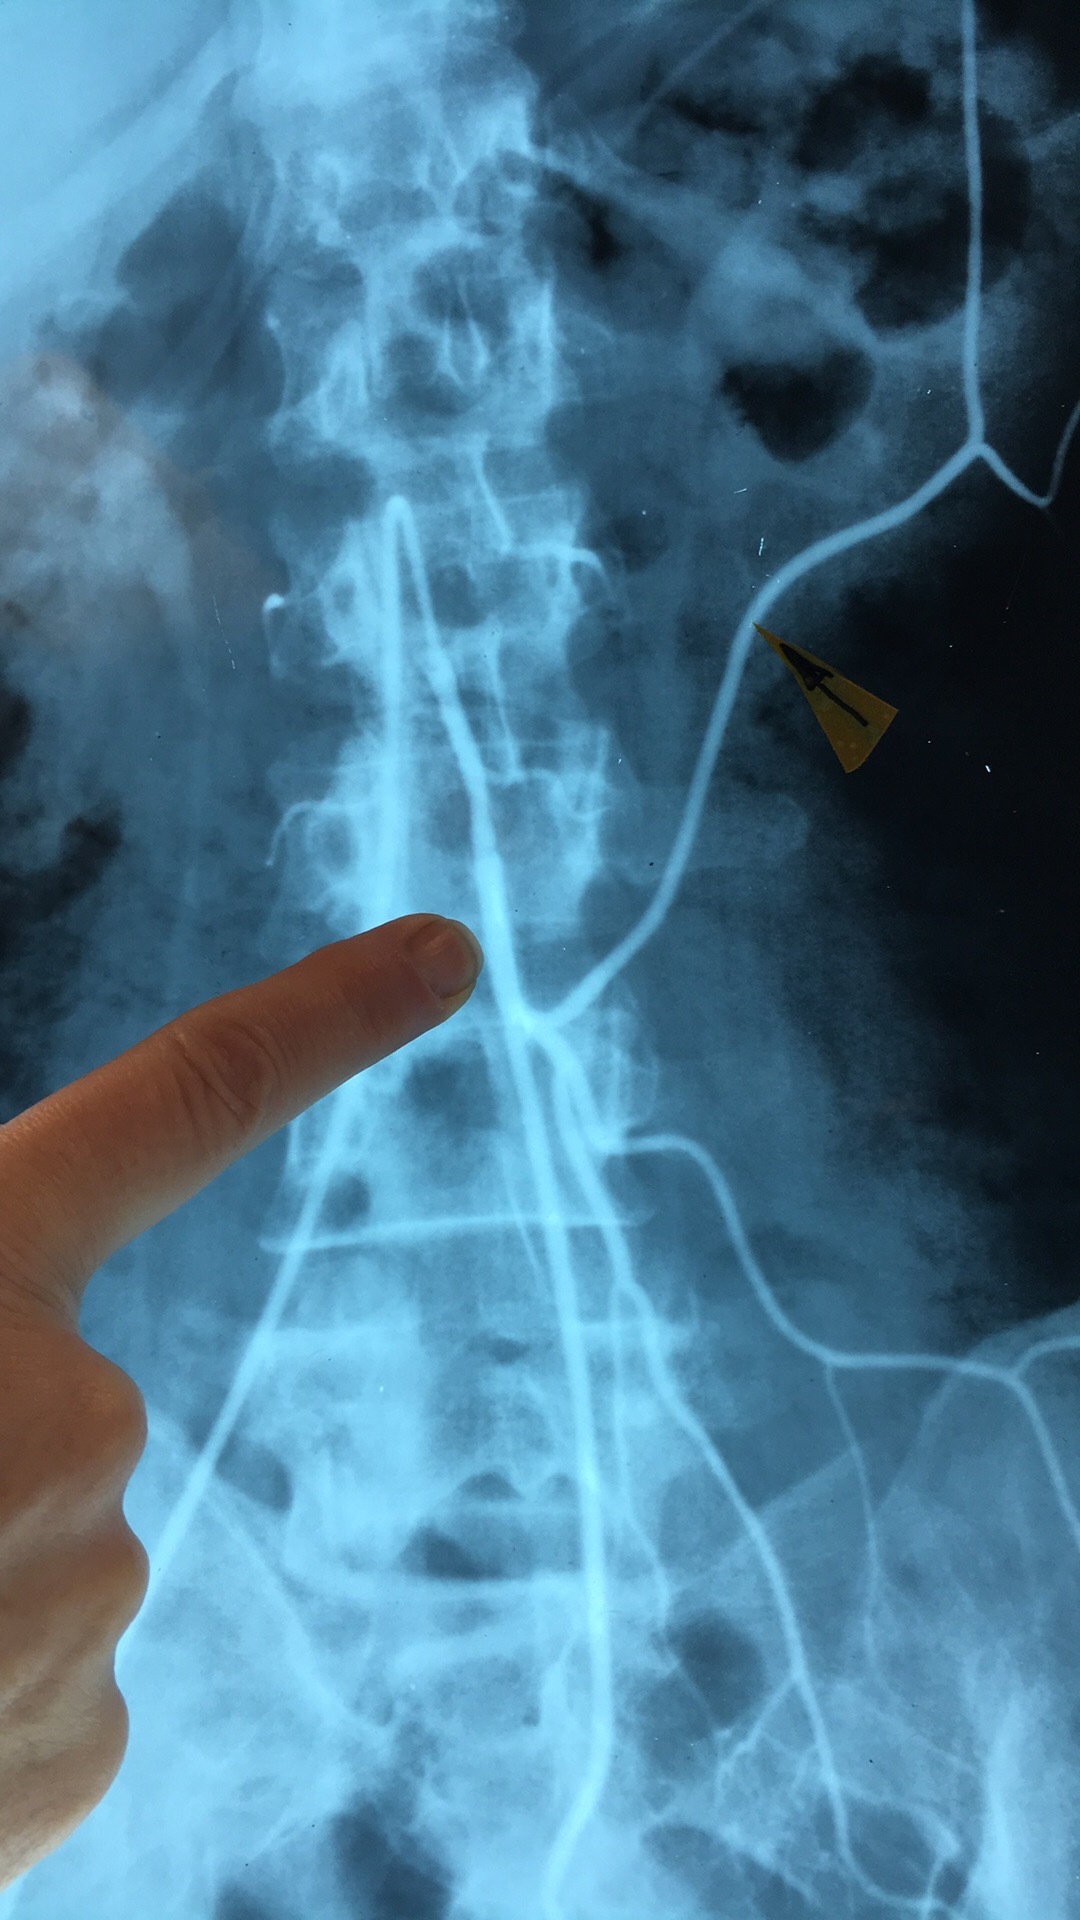

Which artery? What are the 5 branches?

Superior Mesenteric Artery. Intestinal Arteries, Right Colic Art, Middle Colic Art, Ileocolic Art, Inferior Pancreaticoduodenal Art